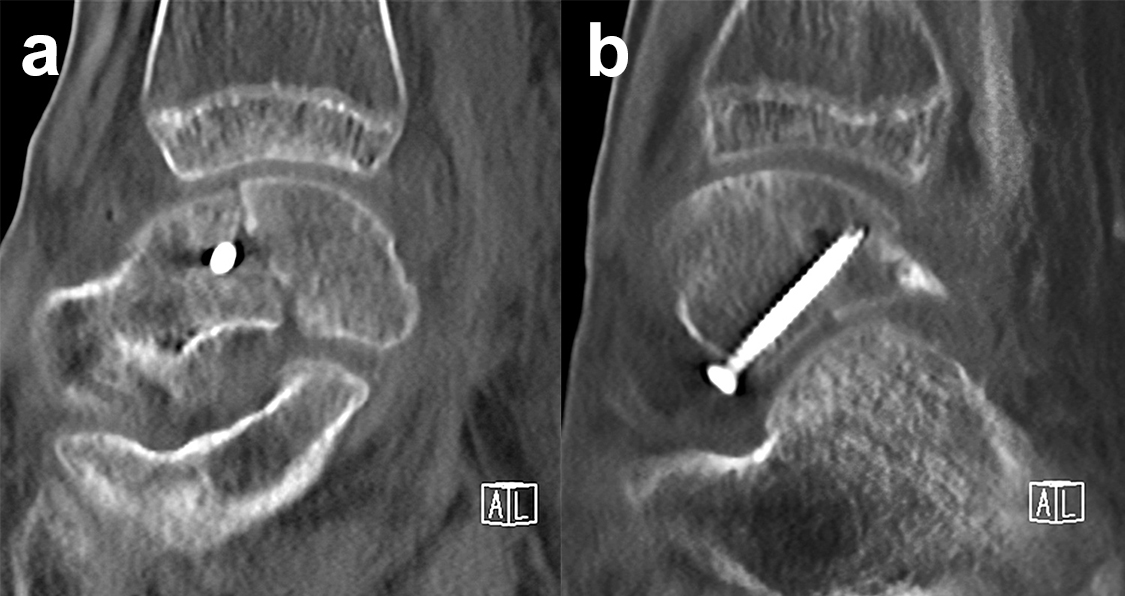

Frakturen des Proc. fibularis tali

Frakturen des Proc. fibularis tali werden im konventionellen Röntgenbild nicht selten übersehen. Sie entstehen häufig nach schweren Distorsionen bzw. im Rahmen subtalarer Luxationen. Eine CT-Kontrolle nach geschlossener Reposition subtalarer Luxationen ist daher obligat (Ab. 15). Der Proc. fibularis tali ist über den anterolateralen Zugang oder schräg verlaufenden Ducroquet-Ollier-Zugang gut zu erreichen. Die subtalare Arthroskopie über anterolaterale und posterolaterale Portale bietet wie bei intraartikulären Kalkaneusfrakturen die Möglichkeit der exakten Kontrolle der geschlossenen Reposition bei einfachen Frakturformen 35. Nach anatomischer Reposition und temporärer Fixierung mittels 1,0 Kirschnerdraht erfolgt die Osteosynthese mittels Kleinfragmentschrauben (2,7 bzw. 3,5 mm), die unterhalb der Knorpel- Knochengrenze eingebracht werden und für eine ausreichende Stabilität sorgen (Abb. 16). Kleinere, nicht anatomisch refixierbare Fragmente, oder Fragmente mit starker Knorpelkontusion werden vorzugsweise exzidiert (Abb. 17). Gleiches gilt für Frakturen des Proc. posterior tali zur Vermeidung einer posttraumatischen Arthrose 23736.